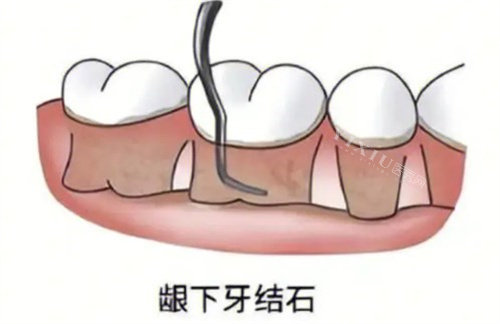

•轻度(地基轻微晃动):刷牙偶尔见血,牙龈有点红,但骨头还好。

这时牙结石主要在牙龈边上,藏得不深,通常1-2次就能清干净。

•中度(地基出现裂缝):牙周袋变深了(大约4-6毫米),牙龈开始萎缩,牙齿容易酸软。

结石已经钻到龈下甚至牙根表面。

•结石分布广不广?要是只有几颗牙问题严峻,次数自然少。

但要是满口牙都遭殃,牙周袋遍布,那就得分片区分批解决,次数就上去了。